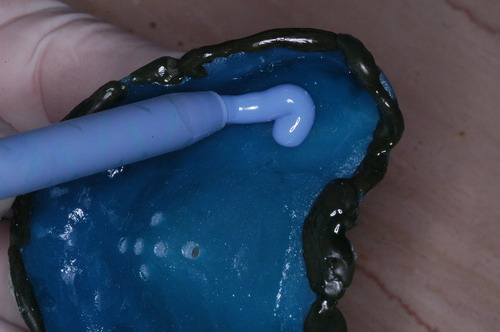

EL USO DEL ARCO GÓTICO DE GYSI , MEDIANTE UNA BÓVEDA PALATINA Y UN APOYO CENTRAL ÚNICO (BO PA YA CU) , EN LA UBICACIÓN DE LA RELACIÓN CÉNTRICA EN UN CASO DE GRAN LAXITUD TENDINOSA CAPSULAR. EL PACIENTE SE PRESENTA A CONSULTA CON UNA EDENTACIÓN PARCIAL, Y GRADO DE MOVILIDAD EXTREMO EN TODAS SUS PIEZAS REMANENTES. SE ESTUDIA EL CASO RADIOGRÁFICA Y CLÍNICAMENTE , Y EL PACIENTE RELATA ESTAR EN ESE ESTADO DESDE HACE MUCHO AÑOS. AL MANIPULAR LA MANDÍBULA EN UN INTENTO DE CONOCER EL ESTADO MUSCULAR DEL SISTEMA, SE OBSERVA UNA GRAN LABILIDAD TENDINOSA CAPSULAR QUE SE MANIFIESTA EN UNA HIPER LAXITUD EN LOS MOVIMIENTOS MANUALMENTE INDUCIDOS DE AMBOS CÓNDILOS DENTRO DE LA CAVIDAD. SE TOMAN IMPRESIONES Y SE MONTA EN UN ARTICULADOR SEMI AJUSTABLE , CORTANDO EN EL YESO LAS PIEZAS QUE SERÁN EXTIRPADAS , CONSERVANDO UNICAMENTE , AMBOS PRIMEROS PREMOLARES INFERIORES , QUE SERÁN UTILIZADOS PARA RETENER MEDIANTE RETENEDORES ELÁSTICOS LA PRÓTESIS INFERIOR , EN LA PRESUNCIÓN DE LA HIPERMOVILIDAD A QUE SERÁ SOMETIDA DADO QUE EN LA GRAN REABSORCIÓN ÓSEA , ES FRECUENTE EL ACERCAMIENTO DE TODAS LAS INSERCIONES MUSCULARES A LA PORCIÓN SUPERIOR DEL REBORDE ÓSEO , LO QUE ATENTARÁ CONTRA LA ESTABILIDAD DE DICHA PRÓTESIS PROVISIONAL. EN UNA PRIMERA SESIÓN CLÍNICO QUIRÚRGICA , SE EXODONCIA TODO EL SECTOR INCISIVO Y CANINO INFERIOR , Y AL OBSERVAR EL REMANENTE ÓSEO CANINO DE AMBOS LADOS , SE IMPLANTA EN FORMA INMEDIATA . TANSCURRIDOS DOS MESES , DONDE LA CICATRIZACIÓN ES ADECUADA , Y LA DINÁMICA MANDIBULAR ACEPTABLE , SE PROCEDE A LA ETAPA QUIRÚRGICA IMPLANTARIA MEDIANTE IMPLANTES SEMI SUMERGIDOS, CON ALGUNAS ZONAS DE REGENERCIÓN ÓSEA GUIADA FIG17 FIG18 FIG19 FIG26 DURANTE LA ETAPA DE CICATRIZACIÓN DE ESTE NUEVO ABORDAJE QUIRÚRGICO , SE ENDODONCIAN AMBOS PREMOLARES INFERIORES CONSERVADOS , LOS QUE EN UN FUTURO , CUANDO YA NO SIRVAN PARA RETENER LA PRÓTESIS REMOVIBLE PROVISORIA INFERIOR , SERÁN CORTADOS COMO RESERVA DE CAPITAL ÓSEO O BIEN COMO ELEMENTO RETENEDOR ANTE CUALQUIER TIPO DE INCIDENCIA IMPLANTARIA. ABORDAMOS LA ETAPA PRIMARIA PROTÉTICA , UNA VEZ TRANSCURRIDOS TRES MESES, MEDIANTE LA UTILIZACIÓN DE CUBETAS INDIVIDUALES , A LAS QUE REALIZAMOS UN RECORTE MUSCULAR EN BASE A STENS VERDE , COMO SI DE UNA PRÓTESIS COMPLETA SE TRATARA. DE ESE MONTAJE OBTENEMOS DOS RODETES DE METACRILATO , PERFECTAMENTE ADAPTADOS A LOS MODELOS FUNCIONALES , A LOS QUE LES OTORGAMOS LA PLANIMETRÍA DERIVADA DEL PARALELISMO CON EL PLANO DE FRANKFURT , Y UNA ALTURA (DV) QUE RESULTA DE LOS MÉTODOS MÉTRICOS DE DIMENSIÓN VERTICAL… Y QUE NOS SERVIRAN ADEMÁS DE TOMAR UNA NUEVA IMPRESIÓN FUNCIONAL MEDIANTE RECORTE MUSCULAR , PARA ADAPTAR UN DISPOSITIVO CONSISENTE EN UNA BÓVEDA PALATINA SUPERIOR , Y UN TORNILLO CENTRAL INFERIOR , LOS QUE DESPUÉS DE UN ENTRENAMIENTO ADECUADO DEL ENFERMO , NOS PERMITIRÁ REPRODUCIR EN EL BÓVEDA , EL ARCO GÓTICO DE GYSI , ENCONTRANDO DE ESTA MANERA LA OCLUSIÓN EN RELACIÓN CÉNTRICA. ACTUALMENTE ESTE MÉTODO HA SIDO RECREADO MEDIANTE LA DENOMINACIÓN DE: FIG50 FIG51 FIG52 OBTENIDO EL DIBUJO DEL ARCO GÓTICO , INSINUAMOS EN EL VÉRTICE DEL MISMO UNA PERFORACIÓN QUE FIJARÁ LA PUNTA DEL TORNILLO EN ESA POSICIÓN: RELACIÓN CÉNTICA FIG55 FIG56 FIG57 CON ESTOS PARÁMETROS SE CONSTRUYEN DOS SOBREDENTADURAS ABROCHADAS EN RÓTULAS SUPRA IMPLANTES , QUE LE OTORGAN FIJACIÓN SUFICIENTE , DANDO A LA OCLUSIÓN TODOS LOS ELEMENTOS DE UNA: OCLUSIÓN MUTUAMENTE COMPARTIDA, REFERENCIA II CON UN ESQUEMA OCLUSAL DE : FUNCIÓN DE GRUPO BILATERAL POSTERIOR DE ACCIÓN CANINA DESPUÉS DE LAS REVISIONES PERTINENTES A LA SEMANA , EL MES Y LOS SEIS MESES DE TERMINADA LA REHABILITACIÓN , SE CITA AL ENFERMO PARA UN NUEVO CONTROL AL AÑO Y MEDIO Y SE OBSERVA UNA PERFECTA SITUACIÓN TISULAR , CLINICA Y RADIOGRAFICAMENTE CONTROLADA , Y ADEMÁS LA PERMANENCIA DEL MISMO ESQUEMA OCLUSAL OTORGADO DESDE EL PRINCIPIO. SE CONTROLA RADIOGRAFICAMENTE Y SE DA EL ALTA DEFINITIVA RECOMENDANDO EL CONTROL DOS VECES AL AÑO. REFERENCIAS: I : II. : III: